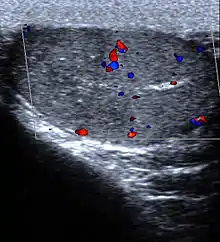

- Spleen: Splenic infarction occurs when the splenic artery or one of its branches are occluded, for example by a blood clot. Although it can occur asymptomatically, the typical symptom is severe pain in the left upper quadrant of the abdomen, sometimes radiating to the left shoulder. Fever and chills develop in some cases.[10] It has to be differentiated from other causes of acute abdomen.